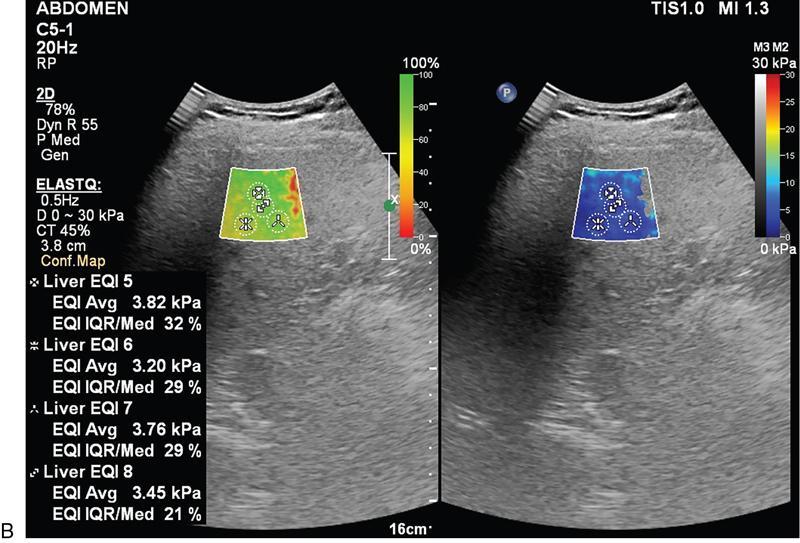

Samarjit Ghuman, Seema Sud, Deeksha Rastogi, Swapnil Sheth, T.B.S. Buxi PLAIN RADIOGRAPHY FOR HEPATOBILIARY IMAGING The diagnostic imaging techniques for hepatobiliary imaging can be intimidating with many techniques/modalities providing the information desired. The job of the diagnostic radiologist includes being familiar with the available choices and pick the ‘best fit’ keeping in mind the pros and cons of each modality, which includes plain X rays, Contrast studies using plain X rays and fluoroscopy, Ultrasound includiojng Doppler and Ultrasound elsastography, CT including multiphase CT and MRI and MRI elastography. Understanding the strengths and weaknesses of every modality as well as the ability to tailor each study individually will help to optimise patient cares. The abdominal radiograph is performed almost exclusively in the supine position and in the AP (anteroposterior) projection. In case of acute abdomen, an erect chest radiograph should also be performed to look for free air under the diaphragm. The standard abdominal radiograph should extend from the diaphragm to the inferior pubic rami, and includes the lateral abdominal wall musculature. Routinely no preparation is required for abdomen radiograph done for hepatobiliary imaging. The radiograph has limited soft-tissue contrast, however, the liver being the largest intra-abdominal organ, casts a perceptible shadow. The margins of the liver can indirectly be seen by outline of adjacent organs like lung, hemidiaphragm, pro-peritoneal fat line, kidney and gas shadows of stomach/colon. The right lobe is seen better than the left lobe of liver. The following pathologies may be visualized on the plain radiograph of the liver. Liver enlargement Liver mass Calcification Increased radiodensity of the liver Decreased radiodensity of the liver An ultrasound is the first line investigation; however, a radiograph may be done for routine evaluation of abdominal pain. The following pathologies may be seen on plain radiograph of the biliary tree. Calculi and Calcifications Gas ULTRASOUND OF HEPATOBILIARY SYSTEM Ultrasonography (USG) is the initial imaging modality of choice for scanning hepatobiliary system. USG is accurate and has high sensitivity and specificity in diagnosing biliary pathologies. Table 9.1.1 shows indications of ultrasound in hepatobiliary system. The real-time nature of ultrasound lends itself to demonstrate mobility of calculi and sludge and the sonographic Murphy sign can easily be elicited during scanning. The main disadvantage is operator dependence, patient’s body habitus, presence of gas which can obscure the visualization of organs, overlying bandages in a postoperative patient and incomplete evaluation in a nonfasting state. USG of upper abdomen should be done after 6–8 hours of overnight fasting. Milk and fatty food should be avoided as they cause contraction of the GB and may cause the GB walls to appear thickened. History of previous surgery, especially cholecystectomy should be elicited. The patient may be positioned in supine or left lateral decubitus position. The GB can be scanned from a high/lateral view, looking through the ribs in supine position or through a sub-costal view in left lateral decubitus position. Position of patient may be changed to demonstrate mobility of structures. The GB is an anechoic structure which is located in the GB fossa along the posterior and inferior aspect of the liver. It has a fundus, body and a neck. It should always be examined in at least two planes (Fig. 9.1.6A and B). The wall of the normal GB should measure 3 mm or less and pathological GB wall thickening can be due to cholecystitis or a neoplastic aetiology. Calculi appear as mobile hyperechoic foci, with distal acoustic shadowing. Other pathologies include polyps and sludge which can be differentiated on the basis of their mobility. The CBD measures less than 6 mm in diameter with increase in the diameter with patient’s age and after cholecystectomy. The CBD is usually scanned in an oblique subcostal plane with the patient in the left decubitus position (Fig. 9.1.7). Dilatation of the intrahepatic biliary radicles is readily assessed with USG and normal intrahepatic biliary radicles are usually not appreciated on USG. Ultrasound of the liver, broadly, is done to assess the size, surface (smooth, coarse or lobulated) parenchymal echogenicity (increased or decreased) vascularity and for presence and evaluation of intrahepatic masses or fluid collections. The liver is divided into right and left lobes by plane of middle hepatic vein which passes through GB fossa and notch of IVC (Cantlie Line). Couinauds classification is the most commonly used system for liver segmental anatomy and described liver into eight functional segments. It is based on distribution of portal and hepatic veins. Every segment has its branch from portal vein, hepatic artery and bile duct (Fig. 9.1.8). Curvilinear transducer (3–5 MHz) is used for routine examination of liver and GB (Fig. 9.1.9). A high-frequency linear transducer (9–11 MHz) (Fig. 9.1.10) can be used to look for subtle irregularity of the liver surface for early Cirrhosis and fine details of GB wall. The liver is scanned in deep inspiration, which causes inferior movement of liver, so that superior borders of the liver are well visualized. Supine position is used for the size of the liver. The measurement is made in sagittal mid clavicular position on right side, in craniocaudal dimension. It is taken from diaphragm to the lower end of the liver. It should be <16 cm and varies with age and sex. The liver is divided into four vertical sectors by three hepatic veins and plane of bifurcation of portal vein divides these 4 sectors in to 8 segments. The right hepatic vein creates vertical plane in the right lobe separating segments V and VIII (anterior) from VI and VII (posterior). The portal vein bifurcation creates a transverse plane and divides these segments into superior (VII, VIII) and inferior segments (V, VI). The left hepatic vein divides the left lobe into medial (IVa, IVb) and lateral sectors (II, III). The left portal vein divides left lobe into superior (Iva, II) and inferior segments (III, IVb). The middle hepatic vein separates medial segments of left lobe (IVa, IVb) from anterior segments of right lobe (V, VIII). Ligamentum teres separates segment III from IVb. Ligamentum venosum separates segment I from IV and II. Cystic duct is an anechoic tubular structure which connects neck of the GB to the extrahepatic biliary tree. In long axis view of GB, the neck of the GB is related to main lobar fissure which appears as a linear echogenic line which runs obliquely between neck of GB and right portal vein. In the right oblique sub coastal view CBD is seen anterior and parallel to portal vein. A series of standardized sections or views may be obtained for liver scanning. Transverse Subcostal View: In this view the probe is angled cephalic and placed transversely under the ribs on the right side and portions both lobes of the liver can be seen (Fig. 9.1.11). Mid Transverse View (Fig. 9.1.12) in this transducer is kept in transverse plane in the midline below the xiphisternum. It visualises the liver in an inferior to superior transverse oblique plane and portions of both lobes of liver can be seen along with right and left portal veins. This view is obtained by angling the transducer superiorly toward the hepatic venous confluence. In this view, we can see the three hepatic veins joining the IVC. Right Parasagittal View for Both Right Lobe and Kidney: This view allows assessment of inferior right lobe of liver. It also allows assessment of relative echogenicity of liver and renal cortex as both are seen together in the same image. Normal liver parenchymal echogenicity is greater than renal cortex and less that renal medulla (Fig. 9.1.14). Parasagittal Right MidClavicular View: In this transducer is kept in sagittal plane in right midclavicular line, and oriented supero-inferiorly. This is the standard view for assessing craniocaudal span of liver (Fig. 9.1.15). Parasagittal View for the Left Lobe: For evaluation of left lobe of liver and lateral segments (2 and 3) (Fig. 9.1.16). This view is obtained along the direction of the main portal vein. CEUS of the liver is done to evaluate Focal Liver Lesions and complements traditional B mode ultrasound and Doppler study. It is a simple, accurate and cost-effective tool complimenting indeterminate CT and MRI findings or for characterization of lesions in patients who cannot receive CT/MRI contrast and can be used in patients with compromised renal function, with minuscule risk of side effects. As CEUS is real-time, microvasculature can be studied along with tissue perfusion kinetics. Indications and uses of CEUS: Contrast agents and technique: Interpretation: Contrast-enhanced ultrasound of a hepatic hemangioma in different phases (Fig. 9.1.19). Limitations of CEUS: Liver elastography is a noninvasive method for diagnosing liver fibrosis. Liver fibrosis is induced by chronic liver disease leading to cirrhosis and liver cancer. Liver biopsy is the gold standard for diagnosing the degree of fibrosis and for staging but it is an invasive method. Elastography helps in analysing the elasticity or the stiffness of the tissue. A stiffer liver tissue indicates fibrosis or chronic liver disease. ARFI is based on the principle of measuring Shear wave velocity. Short duration acoustic pulses which are generated in the tissue and these give rise to shear waves which travel, perpendicular to the ultrasound beam. These shear waves cause tissue displacement followed by recovery. This displacement and recovery depend on tissue stiffness. To monitor these shear waves US beams of low intensity are emitted continuously parallel to the main beam along with the push pulses, and these beams can gather data regarding the tissue stiffness. The shear waves cause tissue displacement and this tissue then recovers from the impulse. From this data the degree of tissue stiffness can be obtained which is displayed either as a map or quantitatively where tissue elasticity is expressed as shear wave velocity measured in meters per second. F0, normal; F1, enlarged fibrotic portal tract; F2, periportal/initial porto-portal septa with intact architecture; F3, architectural distortion with no obvious cirrhosis; F4, cirrhosis. It is also known as Transient Elastography (TE) and works on the similar principle as ARFI, the difference being that B mode ultrasound image is not produced. DOPPLER OF PORTAL VEIN The portal vein divides at the portahepatis into right and left branches. The right portal vein divides into anterior and posterior branches, and the left portal vein divides into medial and lateral branches. Portal vein shows a continuous, forward low-velocity flow (15–28 cm/s) on colour Doppler scanning. The flow is hepatopetal, that is, towards liver and is red in colour as it is flowing towards the transducer. It has an undulating pattern and shows respiratory variation with increase flow in inspiration. It may reflect cardiac variation and shows postprandial increase calibre and flow in healthy individuals. Normal Doppler waveform of portal vein (Fig. 9.1.22). Portal hypertension can be defined as elevated pressure within the portal venous system resulting in impaired blood flow through the liver. INTRAOPERATIVE PANCREATIC AND HEPATIC ULTRASOUND Intraoperative ultrasonography of the pancreas was first described in 1980 by Lane and Glazer. It is an important technique for guidance of both open and laparoscopic surgical procedures of the pancreas. As the transducer is in direct contact with the organ of interest, with no interference with air of adjacent soft tissue, it provides good resolution. It is considered superior to CT and MRI in assessing the intraoperative tumour resectability and vascular invasion and guiding resection. Indications and uses For intraoperative US during open surgical procedures, a high-frequency linear-array transducer or the hockey stick transducer (Fig. 9.1.23) are used which create high-resolution detail of the exposed pancreas. The side-fire curved linear-array transducer is effective for obtaining a wider view of the pancreas and its surrounding structures and for scanning the liver. Intraoperative hepatic ultrasound gives the real-time visualization of the hepatic anatomy and aid for surgical planning and making decision during surgery. Indications and uses Transducer and technique Limitations MULTIDETECTOR CT OF THE HEPATOBILIARY SYSTEM AND CHOLANGIOGRAPHY The cross-sectional plane of the patient is denoted as the x/y plane. The plane along which the table moves is the ‘z’ plane. Multidetector CT denotes more than one detector along the Z-axis, with the latest machines having up to 320 and now even 640 rows of detectors. This provides CT with very fast, high resolution, isotropic images which can be reconstructed in any plane or even curved planes. MDCT scanners can comfortably scan the entire abdomen in 10 seconds or less, thereby allowing visualization of different phases of contrast enhancement. Contrast Media (CM) after administration gets distributed from the intravascular compartment into the interstitial spaces. Intravascular arterial enhancement (for angiography) and parenchymal enhancement have different kinetics. Parenchymal enhancement is directly proportional to total iodine dose being administered and inversely proportional to weight, which is a marker of extracellular volume into which contrast redistributes. Rate of iodine administration has no effect on degree of parenchymal enhancement. As a general rule approx. 500–600 mg of iodine/kg body weight achieves adequate hepatic parenchymal enhancement. For a 60 kg adult, this translates into approx. 100–120 mL of contrast containing 300 mg of iodine per mL. Intravascular or arterial enhancement is controlled by rate at which iodine is administered (flow rate and iodine concentration of CM) iodine flux and duration for which contrast is administered longer injection also leads to better overall arterial opacification due to recirculation effects. This principle is made use of while performing abdominal CT Angiography. Higher iodine delivery rate per unit time using a higher iodine concentration contrast medium also improves conspicuity of vessels and hypervascular lesions such as HCC. For identical parameters, difference in arterial enhancement between patients is dependent on cardiac output with enhancement being inversely proportional to cardiac output. For optimal imaging and enhancement, in multiphase imaging and angiographic studies, contrast material administration and parenchymal or vascular enhancement must be synchronized with CT data acquisition. The two main methods are: Test bolus technique: A test dose of contrast is given and the time to peak enhancement is measured in a ROI placed in a target vessel this information can be used to tailor CT acquisition. Automated bolus Triggering: ROI is placed in target vessel (usually aorta at level of diaphragm) on a plain image. While CM is injected, a series of low dose scans is obtained through the ROI. When the density of contrast reaches a predefined threshold (e.g. 150 HU), at time ‘t’ the scan is automatically triggered. The trigger delay after time ‘t’ is a minimum of 2 sec, and can be programmed to any value. Bolus tracking is nowadays the method of choice for planning contrast medium administration and this technique provides more homogenous opacification. Saline chase is recommended in all multiphase protocols. Significant amount of contrast may be present in the peripheral veins after injection of IV contrast and use of saline chaser leads to better vascular enhancement and lower overall contrast dose (Fig. 9.1.24). Using the above, a standard sequence of acquisitions and contrast enhancement techniques can be tailored to the pathology and organ of interest and pre-programmed into the scanner menu, which includes kVp, mAs, pitch, rotation time, slice thickness etc. This is known as a scan protocol. However, these can be modified as necessary. For example, rotation time can be shortened and pitch can be increased for breathless patients to reduce scan times (Table 9.1.4). Multidetector CT is the workhorse of hepatobiliary imaging. It plays a major role in imaging congenital, traumatic, infective, neoplastic and vascular pathologies of the hepatobiliary system. Scans can be obtained with or without intravenous (IV) iodinated contrast material administration. Multidetector CT scanners are capable of imaging multiple phases at different points of time following injection of contrast and provide dynamic imaging due to fast scan times and rapid coverage of the abdomen. Indications for liver imaging include, but are not limited to: Unenhanced Scan: Hepatic fat estimation, radio opaque biliary calculi. Single Phase Scans: Liver abscess, polytrauma, follow up of known oncologic or benign lesions, abdominal pain, suspected cholecystitis. Multiphase Studies: Evaluation of hepatic masses, imaging in cirrhosis, imaging for resectability, liver donor evaluation, malignancy of GB, hepatic venous outflow obstruction etc. CT Angiography of Hepatic Vessels: Trauma, vasculitis, post-operative bleeding and as a part of multiphase studies. Depending on the indication, scanning protocols can be tailored to highlight the suspected pathology and provide relevant answers for further management (Table 9.1.5). The liver has a dual blood supply, most of which is derived from the portal vein. After injection of contrast, until the portal vein provides recirculated contrast material filled blood to enhance the hepatic parenchyma, the hepatic parenchymal enhancement is relatively poor and dependent only on the hepatic artery. The hepatic arterial phase can be divided into an early arterial phase without any portal opacification, a late arterial or portal inflow phase in which there is some portal vein opacification. This is followed by a portal venous phase in which portal and hepatic veins are enhanced (also called the hepatic venous phase in some articles). In addition, an unenhanced/plain scan and an equilibrium phase can also be acquired. Tumour conspicuity of hypervascular lesions was found to be best on the late arterial or portal inflow phase (Fig. 9.1.25). The early arterial phase is seen up to 10 seconds after trigger, and provides ‘angiographic’ images of hepatic arterial anatomy. This phase is used to provide details regarding arterial anatomy and morphology. Later arterial phase 18–23 seconds, portal venous phase 60–70 seconds and equilibrium phase 180 seconds are obtained after trigger. Equilibrium phase images have been shown to increase detection of hepatocellular carcinoma in cirrhotic patients. The portal venous phase is the standard phase for routine chest/abdomen survey and follow up of hepatic abscesses and hypovascular metastases. Single Phase Scan Protocol: Oncologic follow-up, Liver Abscess – For routine single-phase CT, contrast as per body weight can be injected over 40 seconds and scanning can be done after an empiric delay of 70 seconds from the beginning of injection. This protocol provides good parenchymal enhancement and portal and hepatic vein visualization. Plain scan is optional. Dual-Phase Scan Protocol: Hepatic evaluation in patients with malignancies known to have hypervascular metastases – Neuroendocrine tumours, renal cell carcinoma, thyroid carcinoma, (.) melanoma etc. Late arterial Phase 20–22 seconds and Portal venous phase at 60–70. Plain scan optional. Hepatic Resection Protocol: For patients with known hepatic mass being evaluated for resection. Early arterial phase provides pure arterial or angiographic images. It is obtained at 8–10 seconds post trigger followed by portal venous phase at 60–70 seconds. This is required for arterial and venous anatomy and volumetric evaluation if required. Plain scan is not required. In case a hepatic mass needs characterization as well as resectability planning, late arterial and equilibrium scans may also be done. Indications for angiography are further discussed in the section on angiography. The same biphasic protocol using angiography or arterial phase images is used in patients with trauma suspected to have pseudoaneurysms, hepatic artery thrombosis or dissection in transplant recipients, evaluation of living donors and in patients in whom an angiographic ‘road map’ is required prior to intervention. Triphasic or 4 phase scan Protocol: Standard of care for patients with cirrhosis being evaluated for Hepatocellular carcinoma and for patients being evaluated for hepatic mass of uncertain aetiology. Late arterial phase scan: 20–22 seconds, Portal venous scan at 60–70 seconds and Equilibrium scan at 180 seconds. Plains scans are optional. Our institutional practice is to always do plain scans in patients who have undergone hepatic intervention. Plain scans also help to visualize siderotic and steatotic nodules. A further delayed scan is suggested by some authors at 10–15 minutes for characterization of hepatic masses of uncertain provenance. This is particularly useful in cholangiocarcinoma (Table 9.1.6).

Two main methods used are ARFI (acoustic radiation force impulse) and fibroscan

Technique

Scoring system

Liver Fibrosis Staging

Metavir Score

kPa

m/s

Normal

F0

2.0–4.5

0.81–1.22

Normal–Mild

F0–F1

4.5–5.7

1.22–1.37

Mild-Moderate

F2–F3

5.7–12.0

1.37–2.00

Moderate–severe

F3–F4

12.0–21.0+

2.00–2.64+

Limitations of ARFI